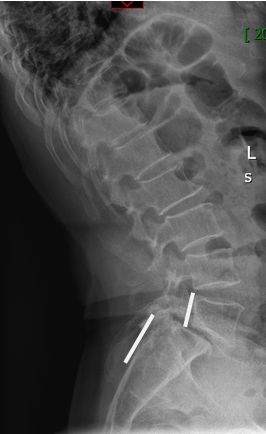

在完善了相关检查后刘阿姨被确诊为腰椎滑脱症—腰5椎体II度向前滑脱。

腰5椎体2度

向前滑脱